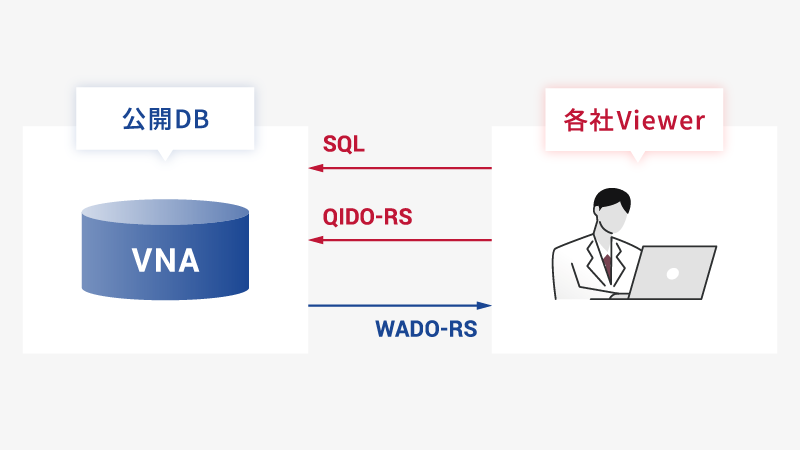

高速アクセス・高速表示

高速アクセス・高速表示

フォーマットやプロトコルの互換性を最大限に確保し、システムの連携を容易にします。

これにより、シームレスなデータの統合・管理が可能となり、時間の節約やスムーズな情報共有を実現。また、端末制限を受けない画像閲覧環境を実現します。

さらにDICOM web(WADO-RS/QIDO-RS)+OCDB(Open Connect Database)に加え、SQLで柔軟に情報を取得することによって画像の高速表示を実現します。